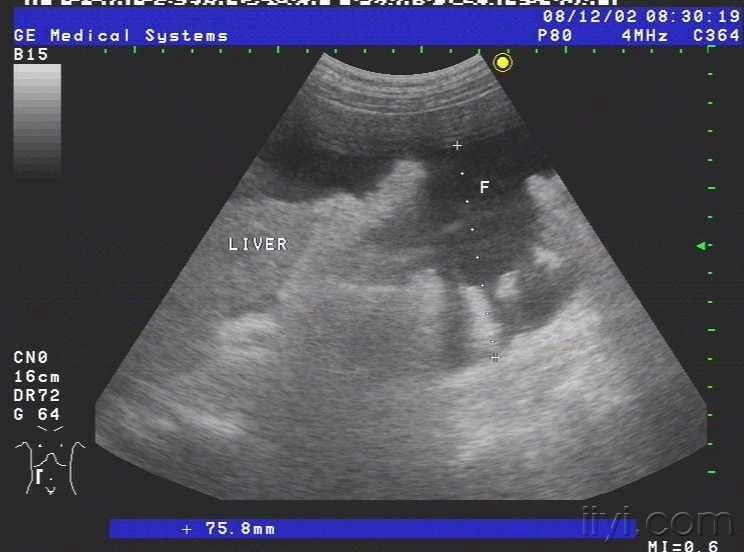

患者女,69岁,病毒性肝炎病史三年余,近半月自觉腹部胀满,来我院就诊,超声查示肝脏被膜不光滑,呈锯齿样,肝内回声不均匀,肝内多发小中等偏强回声团块,大小约1.5cm-3.0cm不等,无明显包膜,境界较清,另于肝右前叶近肝表面见一个大小约4.5cmx2.4cm的椭圆形实性低回声团块,至此处被膜略隆起,团块无明显包膜,伴侧方声影,后方回声增强,内部回声均匀,CDFI未见血流信号.右叶内另见两个类圆形囊性无回声区,肝内管道结构显示不清,肝门脉主干内径约1.1cm.胆囊壁厚1.0cm,囊内透声尚可,脾脏轻度增大,脾门脉无扩张;平卧位腹腔扫查于肝上前间隙肝肾隐窝脾肾隐窝双髂窝均见液性暗区.超声提示:1.肝硬化肝内多发实性团块合并胆囊炎脾轻大及大量腹水;考虑不除外肝癌?

2.肝内多发囊肿.